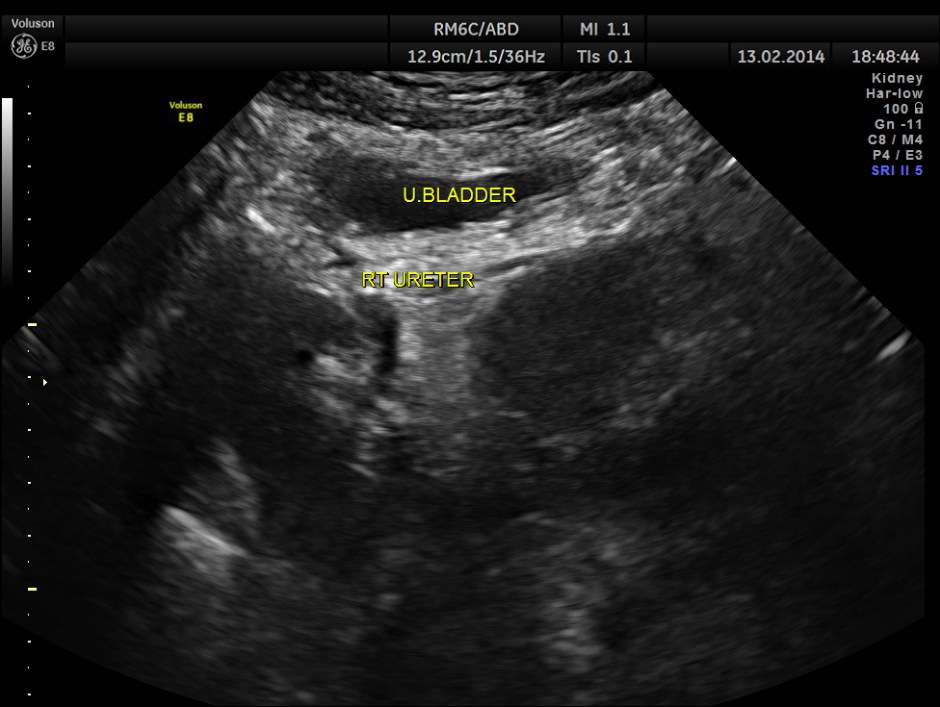

The following are the pictures of the kidney , which show the congenital horse shoe kidneys , placed ectopically in the pelvis. He had no urinary symptoms or low back ache at any time .

the two ureters are shown below separately.